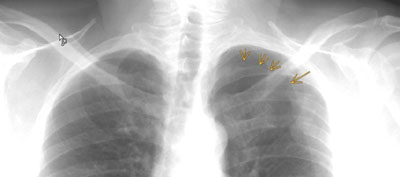

Zu sehen ist eine frische Rippenserienfraktur der 3. bis 5. Rippe links dorsal sowie ein Spitzenpneumothorax links apikal (die Pfeile markieren die Pleura visceralis der zusammengefallenen Lunge).

Beim Spitzenpneumothorax ist nur wenig Luft in den Pleuraraum geflossen. Da diese meist nach oben steigt, sammelt sie sich über der Lunge an. Im Röntgenbild sieht man dann die Luftansammlung über der Lungenspitze, daher der Name "Spitzenpenumothorax". Ein Spitzenpneumothorax wird meistens im Röntgenbild bemerkt und macht wie auch in diesem Fall selten Beschwerden im Sinne einer Dyspnoe. |